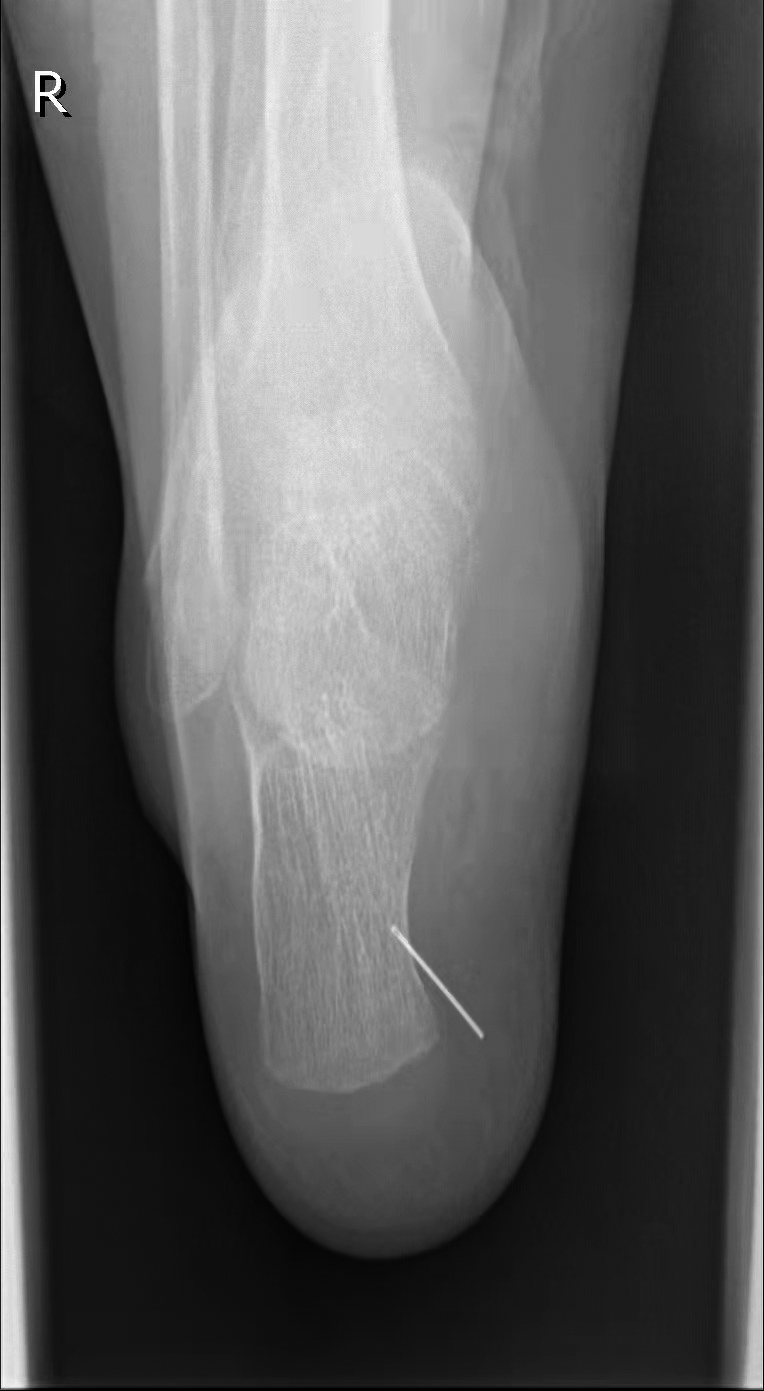

几天前,小杨在爷爷家玩,小杨在床上蹦蹦跳跳时不小心踩到了绣花针,绣花针扎进了右脚踝,当时没什么疼痛的感觉。第二天,小杨妈妈带着他去公园玩了一天。到了第三天,小杨的脚踝开始出现红肿的迹象,妈妈带他去温州市中心医院检查。该院骨科副主任医师楚宇鹏经过检查,发现脚踝处有一个肉眼很难发现的细小针孔,安排其去拍片。片子出来后,着实让小杨妈妈吓了一条,一枚绣花针“藏”在脚踝里。

楚宇鹏说,看似简单的体内金属异物取出有时像“大海捞针”,因为这枚绣花针在体内会游走,需要先将绣花针定位,通过多次拍片找到准确位置再进行手术。医生用了整整一个小时才将绣花针从小杨的右脚踝处取出。